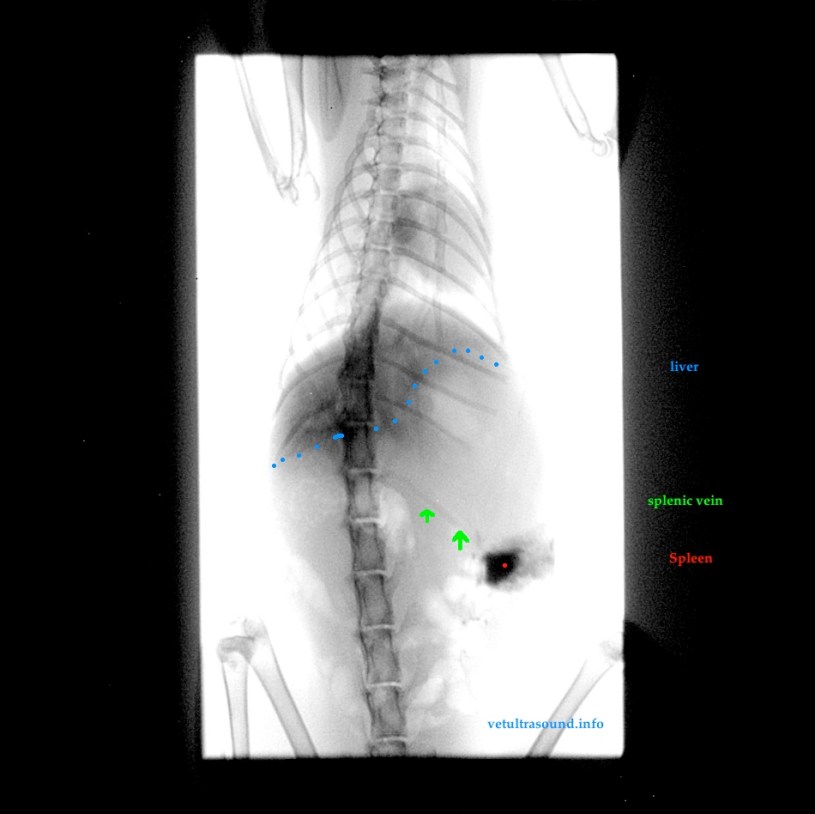

Ο ασθενής βρίσκεται σε γενική αναισθησία. Στη συνέχεια οδηγείται στην αίθουσα του ακτινολογικού και αφού σταθεροποιηθεί σε πρηνή θέση, με υπερηχοτομογραφική καθοδήγηση εισάγεται βελόνα 21G στο σπληνικό παρέγχυμα. Η κατεύθυνση της βελόνας είναι κεφαλουραία και προτιμηταία είναι η είσοδος από το τελευταίο μεσοπλεύριο διάστημα, όποτε αυτό είναι δυνατό, έτσι ώστε η βελόνα να είναι σταθερή κατά την αναπνοή. Αναλόγως του μεγέθους του ασθενή μπορεί να γίνει καθετηριασμός της σπληνικής φλέβας, με έναν through the needle καθετήρα, διαφορετικά η άκρη της βελόνας παραμένει στο παρέγχυμα του σπλήνα. Στη συνέχεια γίνεται έγχυση σκιαγραφικής ουσίας (όπως omnipaque ή xenetix), της οποίας η δοσολογία είναι ανάλογη του μεγέθους του ασθενή.

Αμέσως μετά την έγχυση γίνεται λήψη μίας ακτινογραφίας.

Η εκτίμηση της ακτινογραφίας αφορά την αιμάτωση του ηπατικού παρεγχύματος (αν είναι μειωμένη ή αφορά μόνο τους δεξιούς ή αριστερούς λοβούς), καθώς και την ανίχνευση της πυλαίας κυκλοφορίας.

The patient is under general anaesthesia. After the stabilization of the patient at sternal recumbency on the X-ray table, the left lateral subchondral space is clipped and sterilized. Then a 21G needle is inserted through the last intercostal space, whenever that is possible, into the splenic parenchyma with a dorsocaudal orientation. This placement stabilizes the needle in the spleen during respiration. In larger dogs an attempt to catheterize a splenic vein could be made. Then the contrast media is injected. An xray is taken immediately after the injection. The procedure can be repeated if the xray is taken too late.